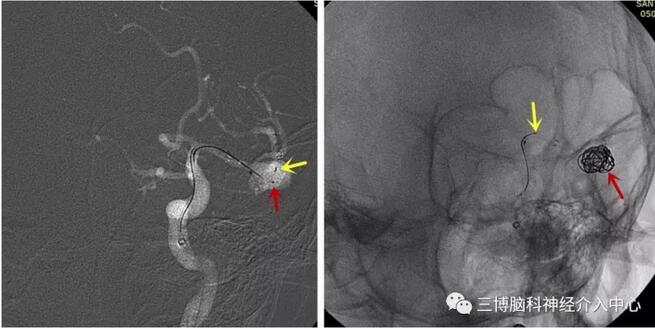

图3 DSA示动脉瘤与载瘤动脉关系(左图为左侧大脑中动脉动脉瘤、右图为左侧椎动脉动脉瘤,红箭为动脉瘤,黄箭为分支血管)

图5 左图示支架微导管及弹簧圈微导管到位(红箭示弹簧圈微导管,黄箭示支架远端(未释放)),右图示弹簧圈成篮满意后释放支架(红箭示成篮弹簧圈,黄箭示支架近端(释放后未解脱))